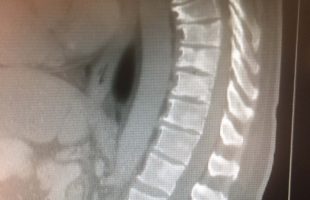

Η Μα. Φο. 26 ετών προ δεκαετίας υποβλήθηκε (αλλαχού) σε χειρουργική επέμβαση στη θωρακο-οσφυική περιοχή της σπονδυλικής στήλης (Σ.Σ.). Η επέμβαση εγένετο προκειμένου να αφαιρεθεί καλοήθης νεοπλασματική εξεργασία (επενδύμωμα) η οποία της είχε προκαλέσει σφιγκτηριακές και νευρολογικές διαταραχές στα κάτω άκρα. Προκειμένου να γίνει εξαίρεση της νεοπλασματικής βλάβης, πραγματοποιήθηκε ευρεία αφαίρεση οπίσθιων στηρικτικών στοιχείων τωνRead more →